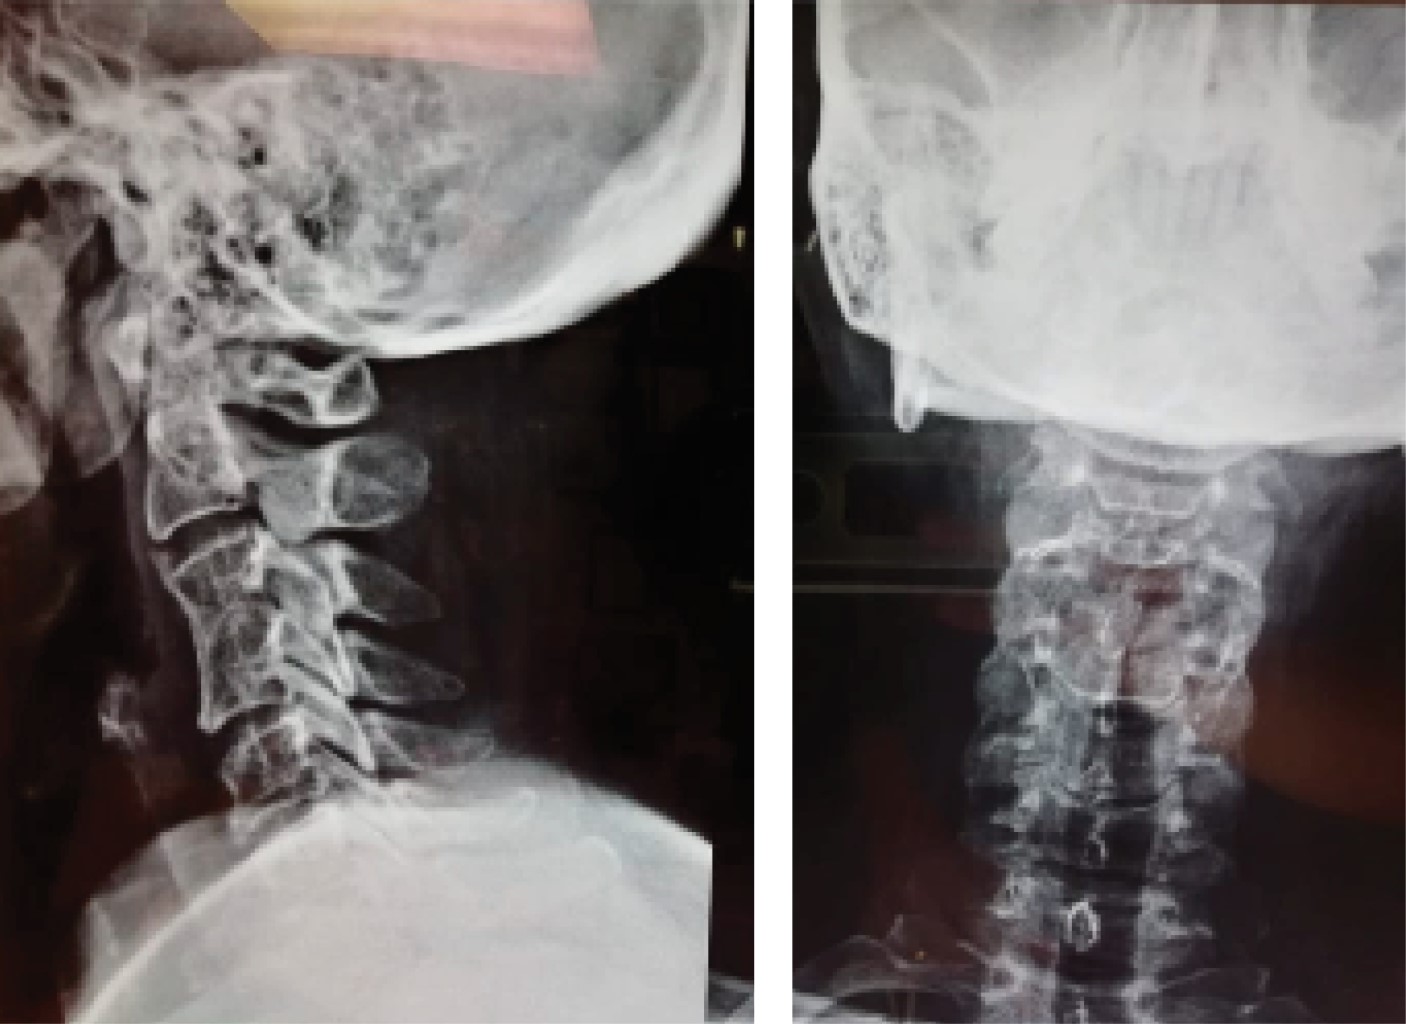

Figure 3